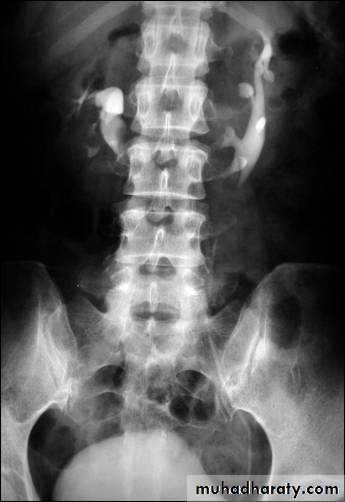

Poly cystic disease

Adult type

Present after the third decade of life , Familial.

Renal parenchyma is replaced by numerous cysts containing fluid , The cysts are of variable size ,

Clinically renal colic, loin mass , heamaturia and hypertension, Renal tissue interposed between the cysts after time dssimcted ended with renal failure

Almost bilateral.

IVU

Large kidney .

Lobulated out-line.

Distortion of pelvi- calyceal system depend on cyst size, number and position.

In advanced cases there is elongation and stretching of minor and major calyces ( spider leg).

In advanced cases IVU shows non-functioning kidney .